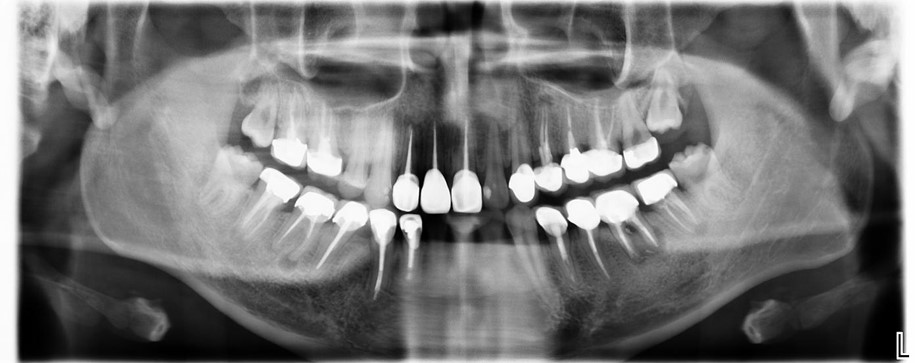

治療前,環口X光,深度蛀牙